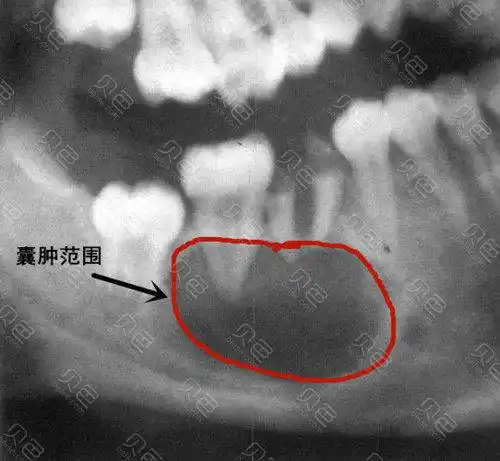

根尖囊肿可以根管治疗吗襄阳根管治疗大概多少钱